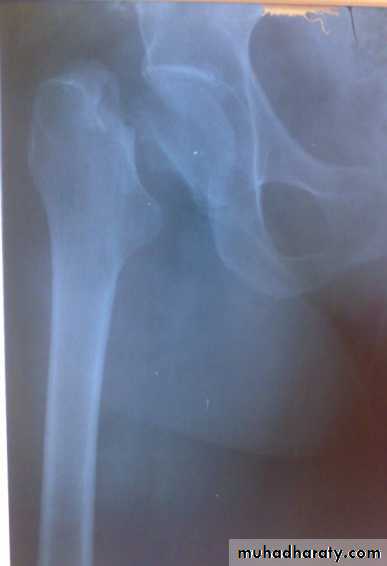

X-ray : AP view : the femoral head is seen out of its socket and above the acetabulum . There may be associated fracture in the femoral head or in the rim of the acetabulum .